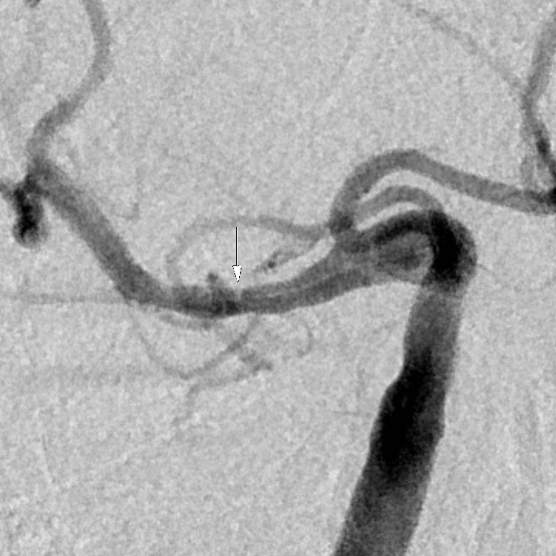

老人家进入医院全面评估后,发现右侧颅内一个主血管存在多节段局限性卡脖子的狭窄,TTP较对侧明显延长,呈缺血状态………,医院多学科讨论评估后,给予第一次外科干预后,患者瘫痪的肢体活动有改善,家人很开心……;在第二次干预之前,又出现了小的新发脑梗塞,继续药物保守治疗,可能还会梗塞;外科干预吧,刚刚出现新发的梗塞,出血风险大,况且又是高龄老年人,血管条件都是个未知数………。本来计划好的二期干预方案受到挑战,面对两难尴尬境地,所有的家人都一时难以决定:向左走?向右走?还是原地踏步进行观望?